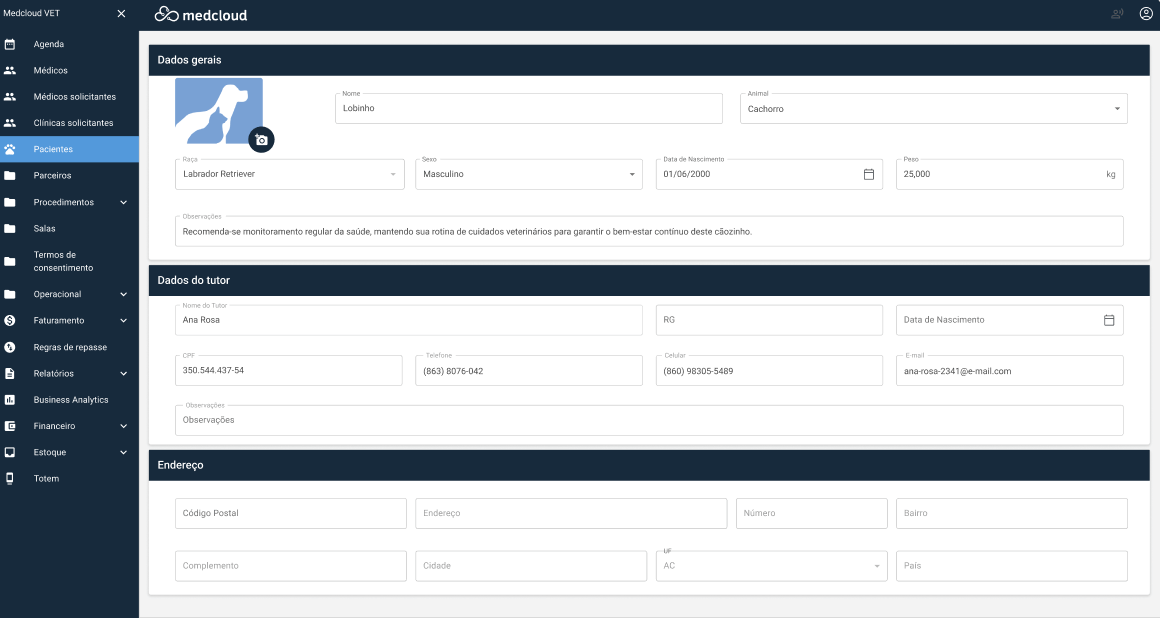

Además de las funcionalidades de Radiología, hemos incorporado recursos en Medcloud RIS, especialmente diseñados para Medicina Veterinaria, como la selección de razas y especies.